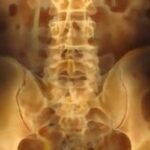

Μία προσθετική συσκευή που μελλοντικά μπορεί να αποκαταστήσει -τουλάχιστον σ’ έναν βαθμό- τη λειτουργία της ουροδόχου κύστης σε ασθενείς, στους οποίους το εν λόγω όργανο έχει αχρηστευθεί εξαιτίας τραύματος στον νωτιαίο μυελό, δημιούργησαν Βρετανοί ερευνητές.

Η ζημιά στα νεύρα δεν επιτρέπει στον ασθενή να νιώθει πότε γεμίζει η κύστη του με ούρα ή να την ελέγχει. Η συσκευή μπορεί να «διαβάζει» τα ηλεκτρικά σήματα των λιγοστών νεύρων που έχουν απομείνει γύρω από την ουροδόχο κύστη κι έτσι ο ασθενής είναι σε θέση ξανά να αποκτά τον έλεγχο του οργάνου και των ούρων του, βελτιώνοντας την ποιότητα της ζωής του.

Οι ερευνητές, με επικεφαλής τον δρ. Ντάνιελ Τσου του Πανεπιστημίου του Κέμπριτζ, που έκαναν τη σχετική δημοσίευση στο ιατρικό περιοδικό «Science Translational Medicine», σύμφωνα με το BBC, χρησιμοποίησαν ηλεκτρόδια που συνέδεσαν στα εναπομένοντα νεύρα της κύστης και έκαναν με επιτυχία τις σχετικές δοκιμές σε αρουραίους.

Το επόμενο βήμα θα είναι η σμίκρυνση των εξαρτημάτων, ιδίως αυτών που επεξεργάζονται τα νευρικά σήματα, ώστε η τεχνολογία να καταστεί δυνατό να αξιοποιηθεί για ανθρώπινη χρήση. Στόχος είναι, εκτός από τη συσκευή με τα ηλεκτρόδια που θα εμφυτεύεται στην περιοχή της κύστης, ο ασθενής να διαθέτει μια δεύτερη συνδεδεμένη φορητή συσκευή, με το κατάλληλο πλήκτρο, που θα δίνει εντολές κατά βούληση στην κύστη για να αδειάζει από τα ούρα.